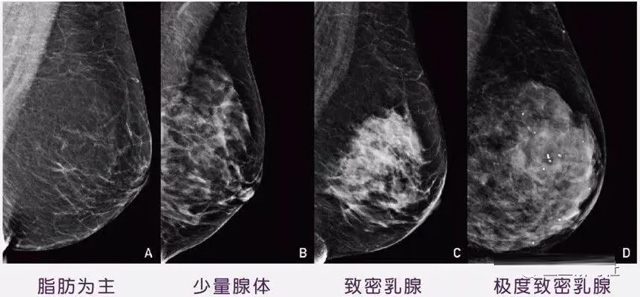

女性乳腺的自我檢查,特別是注意有小結節(jié),腫塊,乳頭有液體滲出情況,需要通過乳腺DR,X光線,磁共振等影像技術檢查。胸的大小跟乳腺癌沒多大關系,乳腺的密度大發(fā)病率高一些,胸小脂肪少致密性大。更容易乳腺癌。這個還不能通過自我檢查來確認。致密乳腺組織看上去是白色或淺灰色需要通過乳腺X射線檢查。

乳腺X射線有輻射,40歲以下的女性沒有高危因素跟臨床特征,醫(yī)生都是不建議使用鉬靶檢查。乳腺超聲無創(chuàng)無輻射,對乳腺組織分辨率高??梢詫⑷橄倌[塊從致密型乳腺組織中輕松查出來,多普勒模式檢查乳腺及病變,超聲小于1厘米的病灶非腫塊性乳腺癌檢出率低。超聲檢查結果依賴醫(yī)生水平和經驗,乳腺DR超聲推動乳腺超聲圖像的標準化,提高檢查的準確率。對乳腺組織內的細小鈣化灶, 從范圍、乳腺X射線形態(tài)以及分布特點上進行定性診斷。造影劑增強型乳腺X線攝影靜脈注射碘化造影劑結合乳房X線攝影。磁共振MRI對乳腺癌研究的深入對軟組織具有較高的分辨率等特點,在臨床上被廣泛認可。乳腺CT的探測器圍繞著乳房成像,無痛無擠壓,3D乳房圖像乳腺病灶的大小、數(shù)量、形狀、位置以及血管分布。一次掃描可創(chuàng)建多達兩千張投影圖像 。乳腺PET,適合普通人群和乳腺癌高危人群早期檢測,發(fā)現(xiàn)極早期微小病灶并明確定性。